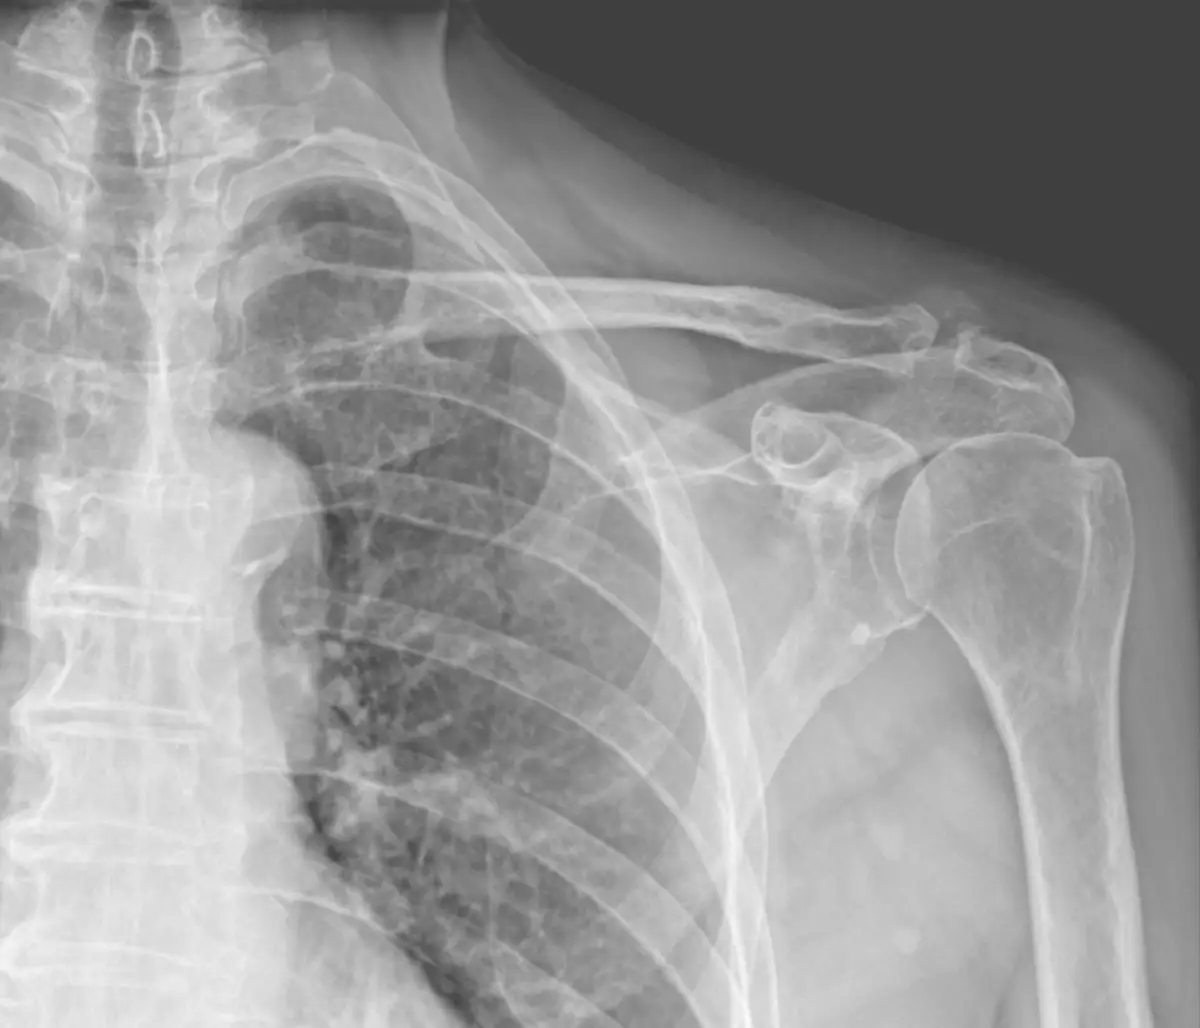

Upadek, wypadek, chwila nieuwagi – i nagle pojawia się ostry ból w okolicy barku. Diagnoza lekarska brzmi jak wyrok: uszkodzenie stawu barkowo-obojczykowego (AC), a w badaniu klinicznym charakterystyczny „objaw klawisza”. To częsty scenariusz, z którym spotykam się w moim gabinecie fizjoterapii w Sosnowcu.